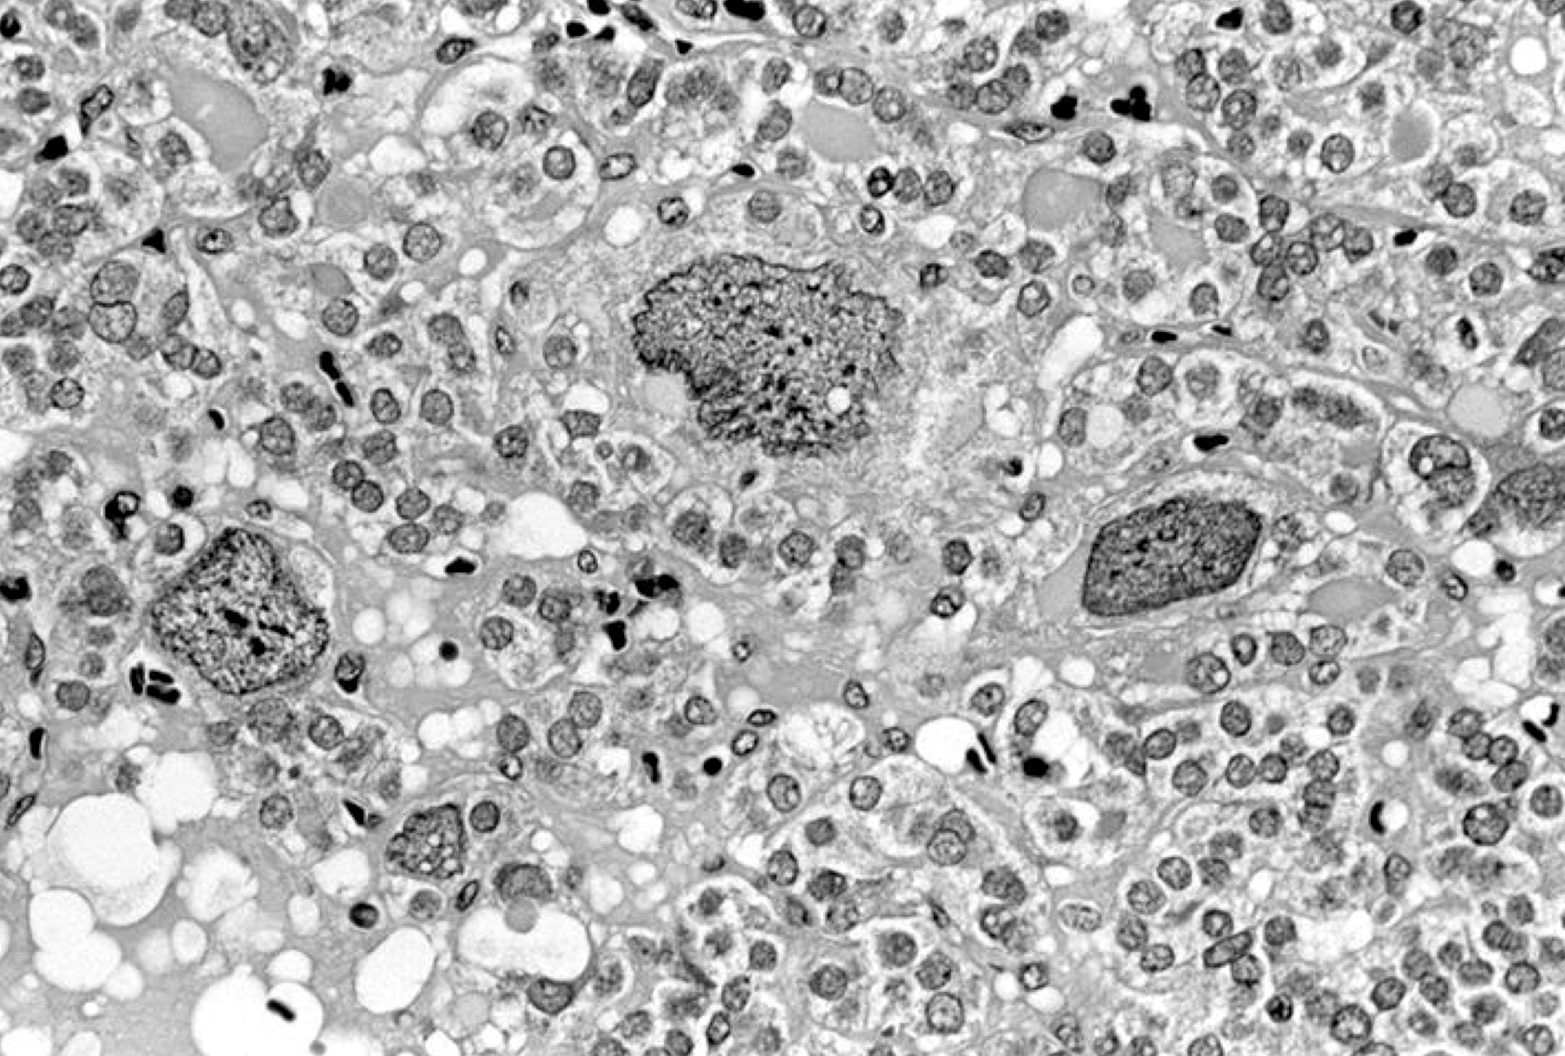

Electron microscopy description

- Similar to normal thyroid gland and hyperplastic nodules

- Hyperfunctioning follicular adenomas: organelle rich cytoplasm, especially rough endoplasmic reticulum; numerous, long microvilli on surface (Am J Clin Pathol 1982;78:299)

- Clear cell follicular adenomas: cytoplasmic vesicles of variable size; these may be dilated cisternae of the rough endoplasmic reticulum or mitochondria, lysosomes or endocytic vesicles (Virchows Arch A Pathol Anat Histol 1978;380:205)

Electron microscopy images